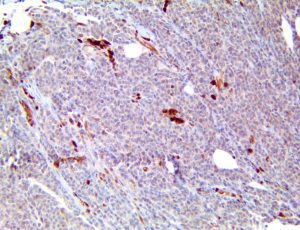

It is the ICU physician who is most likely to witness one of the deadliest manifestations of the abnormal immunological response, the cytokine storm syndrome (CSS). This response is also referred to by some as the cytokine release syndrome (CRS). CSS is characterized by continuous activation and expansion of macrophage and lymphocyte populations, which secrete large amounts of cytokines, causing the cytokine storm. This massive cytokine release is akin to hemophagocytic lymphohistiocytosis (HLH) disease, a syndrome characterized by initial unchecked and persistent activation of cytotoxic T lymphocytes and NK cells.

Clinical and laboratory manifestations of HLH include fever, enlarged liver and/or spleen, neurologic dysfunction, coagulopathy, liver dysfunction, cytopenias (i.e., low levels of erythrocytes, leukocytes, and/or platelets), hypertriglyceridemia, hyperferritinemia, hemophagocytosis, and eventually diminished NK cell activity as the immune system becomes progressively paralyzed. HLH can be familial (primary HLH) or secondary to another disease process (sHLH), such as rheumatic disease, in which it is referred to as macrophage activation syndrome (MAS, characterized by elevated ferritin).